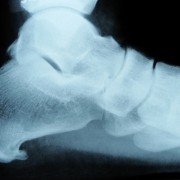

Wat is een hielspoor?

/door Anke KremersEen hielspoor is een klein aangroeisel aan de voor- en onderzijde van de hiel. Het ontstaat door jarenlang staan, lopen en springen. De platte peesplaat onder de voet ook wel de ‘fascia plantaris’ genoemd trekt jarenlang aan de hiel, waardoor de hiel soms de neiging heeft om extra bot aan te maken. Hierdoor ontstaat een soort aangroeisel de zogenaamde ‘hielspoor’. Deze is goed zichtbaar op een röntgenfoto.